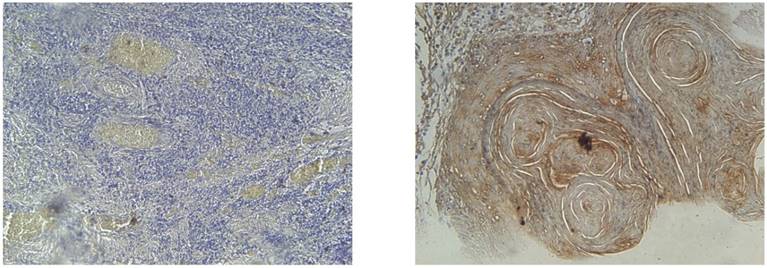

Kaplan-Meier disease free survival (left) and overall survival (right) curves in 100 OSCC patients selected according to EGFR status

Living status was taken as the time interval from primary treatment until death or last follow-up taken at 5 years (60 months. Mean 5 year survival time for our population was 43 months with an overall survival rate of 56%. Univariate analysis showed that AJCC stage (p=0.004), final N stage (p=<0.001), EGFR expression (p=0.048) and EGFR staining intensity (p=0.015) all had a significant effect on 5 year survival. Moreover, EGFR expression (p=0.056) and AJCC stage (p=0.003) were also proven to be independent determiners of 5 year survival on the multivariate analysis (Table 3A and Table 3B).

Disease free survival and EGFR overexpression

Recurrence was defined as any relapse, locoregional or distant; however in our data there was no distant metastasis. Overall mean disease free survival time was 82 months with a recurrence rate of 65%. Univariate analysis revealed AJCC stage (p=0.01, final N stage (p=<0.001), EGFR expression (p=0.01) and EGFR staining intensity (p=0.01) to be significantly associated with recurrence of patients. However, on the multivariate analysis only final N stage (p=<0.001) and EGFR expression (p=0.004) had a strong independent influence on disease free survival (Table 3A and Table 3B).